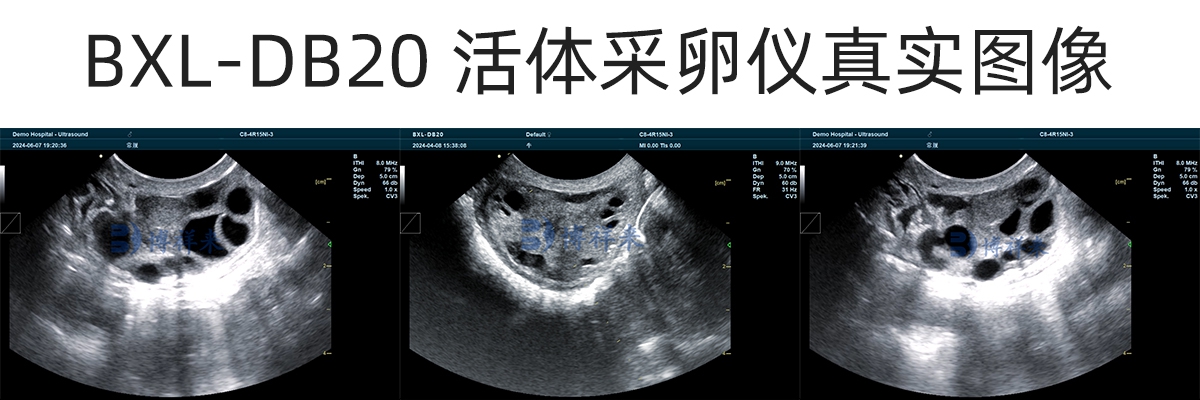

在操作过程中,兽用B超机实时显示卵巢结构和卵泡位置,操作人员在超声引导下,将穿刺针精准进入卵泡,通过负压将卵泡液和卵母细胞吸出,从而完成活体采卵。

牛用B超的清晰度和稳定性,是牛活体采卵成功率的关键基础。

成像清晰度高,能准确分辨卵泡边界

只有在清晰、稳定的超声图像引导下,才能提高采卵成功率,同时降低误穿刺风险。